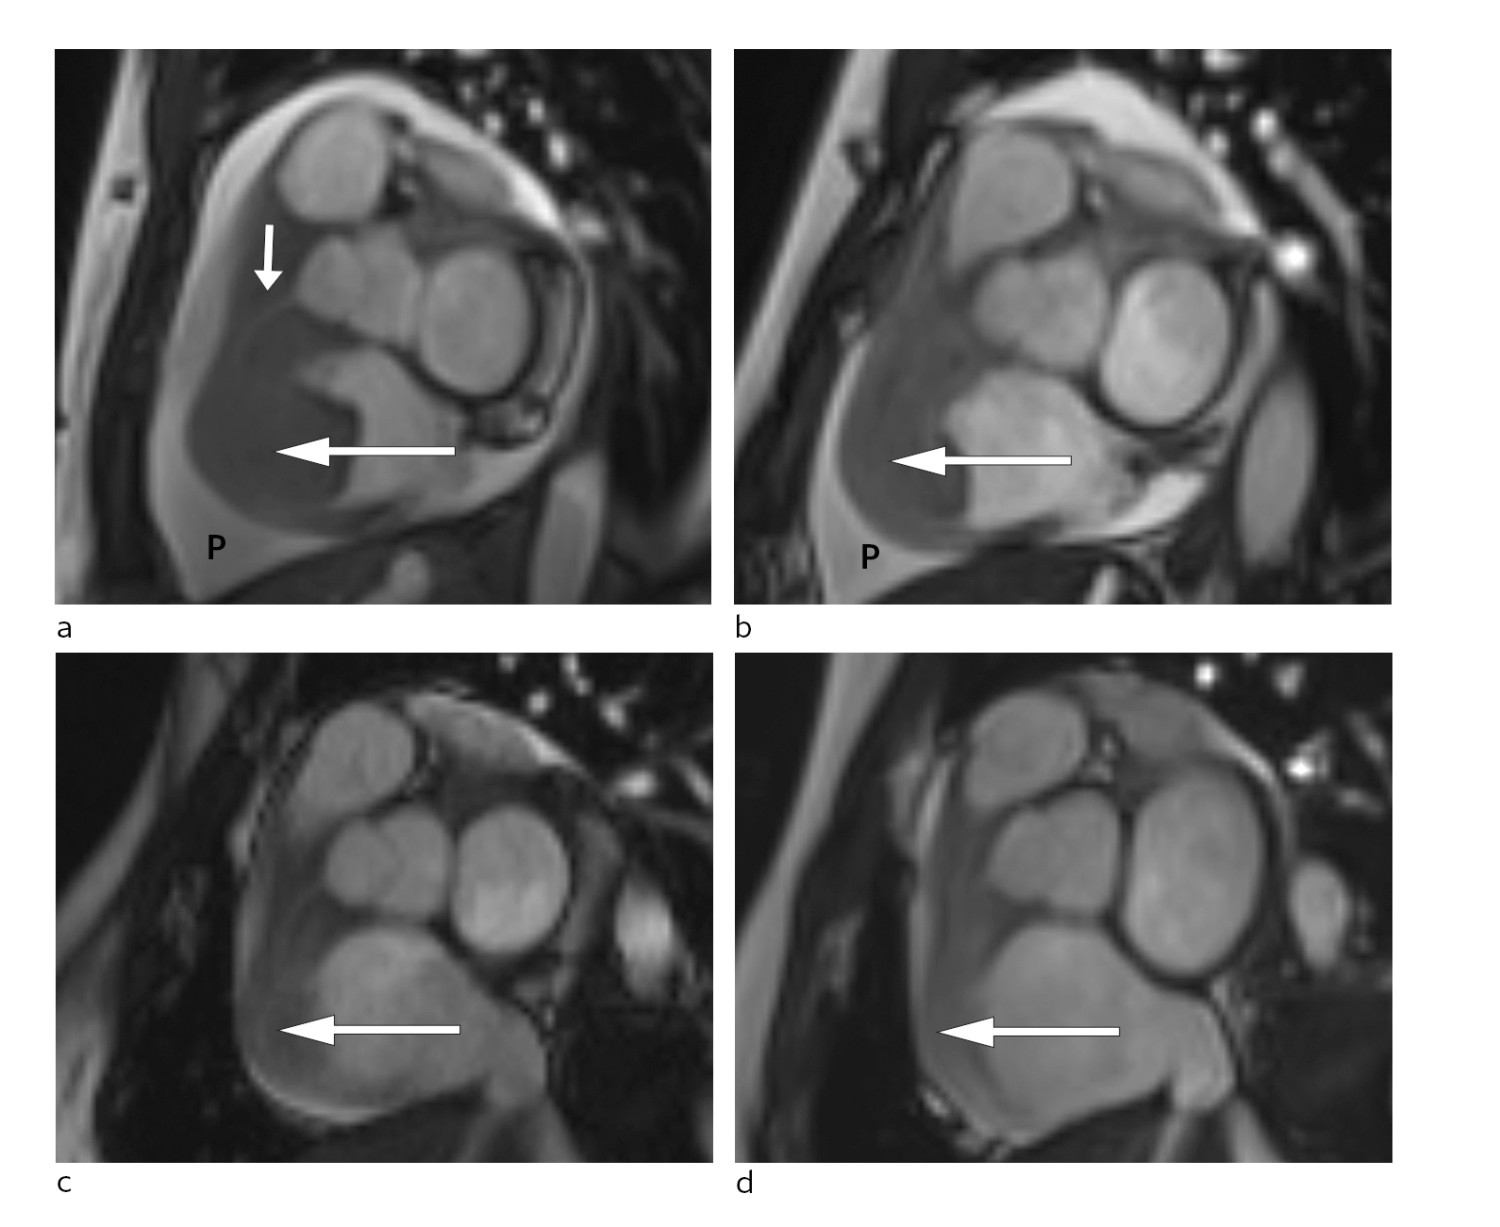

Etter funnet av bilyden vart det gjort ein orienterande ekkokardiografi i akuttmottaket. Denne viste to store oppfyllingar på høgre side i hjartet. Den største oppfyllinga målte 3,5 x 3 cm, var lokalisert i atriet og adherent til trikuspidalklaffeapparatet. I tillegg var det ei mindre oppfylling som òg penetrerte inn i høgre ventrikkel.

Det var tydeleg obstruksjon av den normale blodstraumen i trikuspidalostiet. I tillegg vart det påvist perikardvæske, mest uttalt langs høgre ventrikkel, med største brem målt til 1,5 cm, men utan at det var haldepunkt for tamponade. Det var normale forhold over mitral- og aortaklaff på venstre hjarteside. Funnet vart stadfesta med CT-undersøking av hjartet, som også gav mistanke om infiltrasjon av tumormassar i veggen til høgre ventrikkel med perikard (fig1).

Allereie timar etter at behandlinga tok til merka pasienten avtakande brystsmerter og mindre dyspné. To dagar seinare var det mogleg gjennomføre MR-undersøking av hjartet. Denne bekrefta persisterande tumormassar i høgre atrium og høgre ventrikkel med gjennomvekst av ventrikkelvegg og samanlodding av trikuspidalsegla (fig 3).

Pasienten vart i denne fasen observert i hjarteovervakingsavdelinga. Det vart ikkje observert arytmiar eller andre komplikasjonar til behandlinga. Ho fekk lågdosert fraksjonert heparin som tromboseprofylakse. Repetert MR-undersøking som vart gjort tre dagar etter oppstart med CHOP-regimet, viste betydeleg regress av oppfyllinga i høgre hjartehalvdel og nærast total regress av intrakavitære komponentar. Den atrioventrikulære opninga på høgre side var betydeleg større enn ved den initiale MR-undersøkinga (fig 3).

Pasienten gjennomgjekk ytterlegare blokkurbehandling. Radiologisk evaluering etter andre behandling viste nærast total regress av tumormanifestasjonat i abdomen (fig 3). Ein har heldt fram med R-CHOP-regimet, som har helde sjukdomen i remisjon sidan.